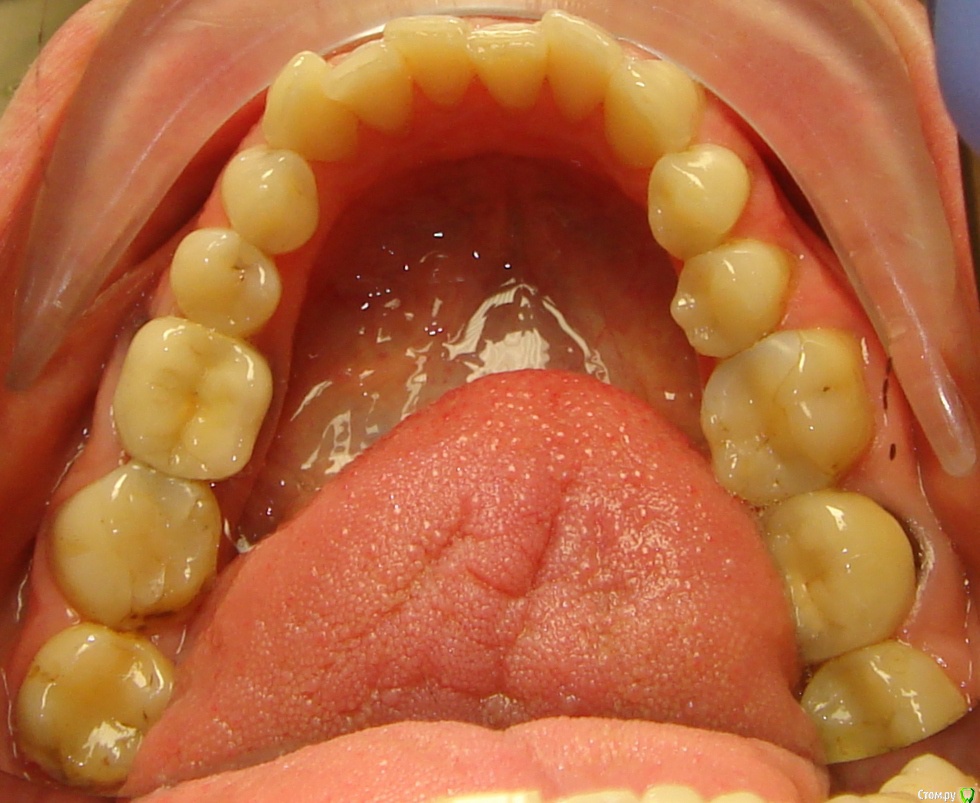

Opdihatop Опубликовано 16 апреля, 2017 Поделиться Опубликовано 16 апреля, 2017 Здравствуйте, коллеги! Что вы думаете по поводу этого случая? Объективно: вертикальный рост, первый костный класс. Незначительная протрузия резцов в/ч, нормальный наклон резцов н/ч. 15 зуб ретенирован. Значительное сужение в/ч, сужение н/ч.Вопросов 2: 1) Тянуть ли 15 зуб? 2) Планирую расширять при помощи SARPE, что делать с образовавшимся местом (которое и так сейчас уже есть)? Мне кажется такие большие реставрации будут некрасивыми. Ссылка на комментарий

Brigita Опубликовано 16 апреля, 2017 Поделиться Опубликовано 16 апреля, 2017 (изменено) Здравствуйте, коллеги! Что вы думаете по поводу этого случая? Объективно: вертикальный рост, первый костный класс. Незначительная протрузия резцов в/ч, нормальный наклон резцов н/ч. 15 зуб ретенирован. Значительное сужение в/ч, сужение н/ч.Вопросов 2: 1) Тянуть ли 15 зуб? 2) Планирую расширять при помощи SARPE, что делать с образовавшимся местом (которое и так сейчас уже есть)? Мне кажется такие большие реставрации будут некрасивыми.1) а куда его?2)Реставрации передних зубов имеется ввиду? Не такой большой промежуток, можно и реставрацию, если виниры не может позволить. расширение на SARPE - в таком возрасте без хирургии маловероятно, Вы же сами знаете, получите зубоальвеолярное небольшое расширение и наклон. Такой тонкий биотип, что там еще с кортикалкой будет. Мосты спаянные, вкладки. Чтобы узнать положение 5го надо КТ сделать, где у него корень - пойдет ли. Он видимо в небной костиА вообще - отдайте ее ортопедам. Она сама то что хочет? Изменено 16 апреля, 2017 пользователем Brigita Ссылка на комментарий

Brigita Опубликовано 16 апреля, 2017 Поделиться Опубликовано 16 апреля, 2017 Черные треугольники заполнить и рецессии убрать. я вот чего то не понимаю наверно.. где треугольники, которые она хочет убрать? я вижу диастему, трему 22-21, кариес 11-12, многочисленные рецессии, плохие ортопедические коронки, неправильно выполненные вкладки ( а может правильно? я не ортопед), скученность нижних зубов. А вообще вот интересно - в каком возрасте максимально возможно расширение на SARPE, у кого какой опыт? Ссылка на комментарий